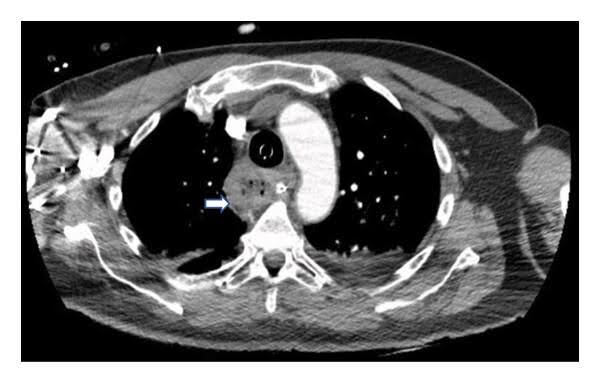

Fig. 1: CT thorax1

Here, an almost complete atelectasis of the left lower lobe and a distended oesophagus were seen. The next step was a gastroscopy to get to the bottom of the matter.